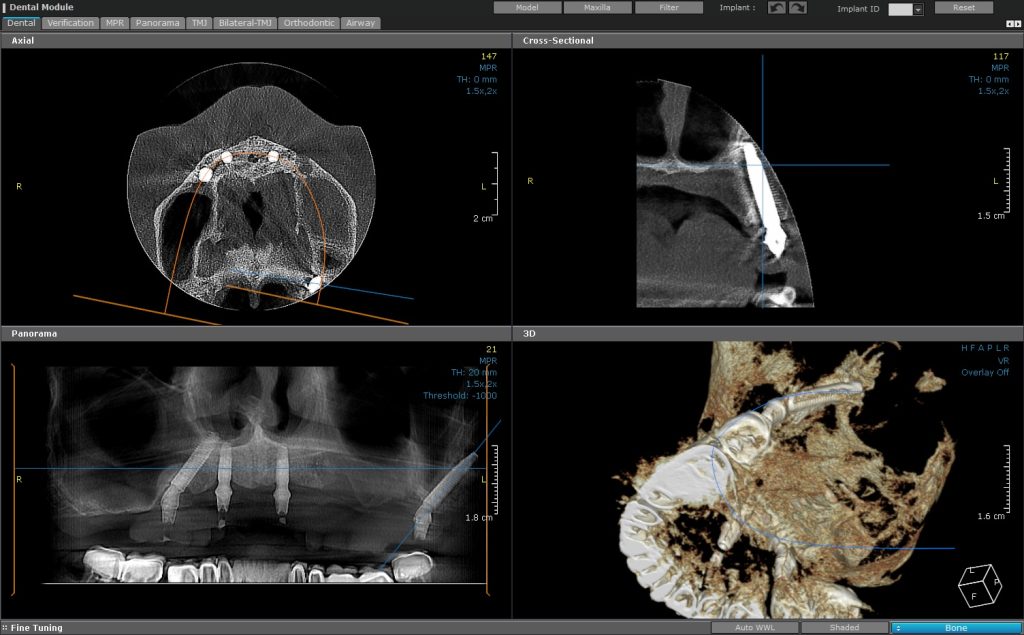

CBCT analysis of a pterygoid implant showing the anchorage in sphenoid and palatal bone

Pterygoid implant 3d position confirmed